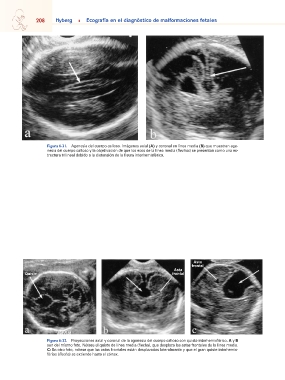

Figura 6-31. Agenesia del cuerpo calloso. Imágenes axial (A) y coronal en línea media (B) que muestran age-

nesia del cuerpo calloso y la objetivación de que los ecos de la línea media (flechas) se presentan como una es-

tructura trilineal debido a la distensión de la fisura interhemisférica.

•Aumento de la separación de los hemisferios con una cisura en la línea media anterior se asocia con agenesia del cuerpo

interhemisférica resultante de la ausencia de la comisura ce- calloso en el 50% de los casos126. Merece la pena mencionar,

rebral principal. En tales circunstancias, la ecografía demuestra sin embargo, que los lipomas generalmente no suelen ser de-

tres líneas ecogénicas que discurren paralelas en la parte su- mostrables en el segundo trimestre, y tienden a aparecer tar-

perior del cráneo, siendo la del medio la hoz cerebral y las de díamente en la gestación125.

los laterales los bordes mediales de los hemisferios separa- •La ausencia de la arteria pericallosa, una rama de la arteria

dos (Fig. 6-31). callosa anterior que normalmente discurre a lo largo de la cara

Figura 6-32. Proyecciones axial y coronal de la agenesia del cuerpo calloso con quiste interhemisférico. A y B

son del mismo feto. Nótese el quiste de línea media (flecha), que desplaza las astas frontales de la línea media.

C: En otro feto, nótese que las astas frontales están desplazadas lateralmente y que el gran quiste interhemis-

férico (flecha) se extiende hasta el córtex.